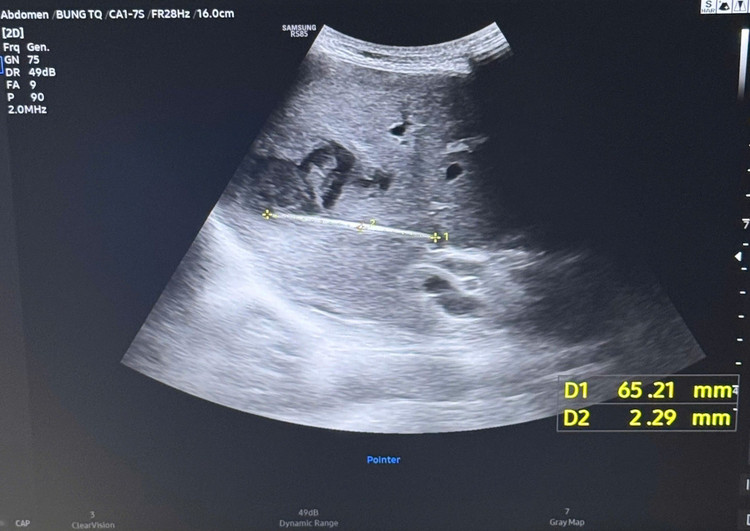

Khi tiến hành siêu âm kỹ hơn, ê-kíp phát hiện một dị vật cản quang xuyên trong nhu mô gan, chiều dài ước tính khoảng 6-7cm. Ngay sau đó, bệnh nhân được chỉ định chụp cắt lớp vi tính (CT scan) ổ bụng.

Kết quả cho thấy có một dị vật dạng que dài nằm hoàn toàn trong nhu mô gan, kèm theo ổ áp xe sâu. Trước nguy cơ biến chứng nặng nếu không điều trị kịp thời, ê-kíp khoa Nội tiêu hóa đã nhanh chóng hội chẩn cùng khoa Ngoại Gan Mật Tụy, thống nhất phương án phẫu thuật lấy dị vật, dẫn lưu ổ áp xe, kết hợp điều trị kháng sinh phù hợp.

Hình ảnh dị vật gây ổ áp xe trong gan - Ảnh BVCC